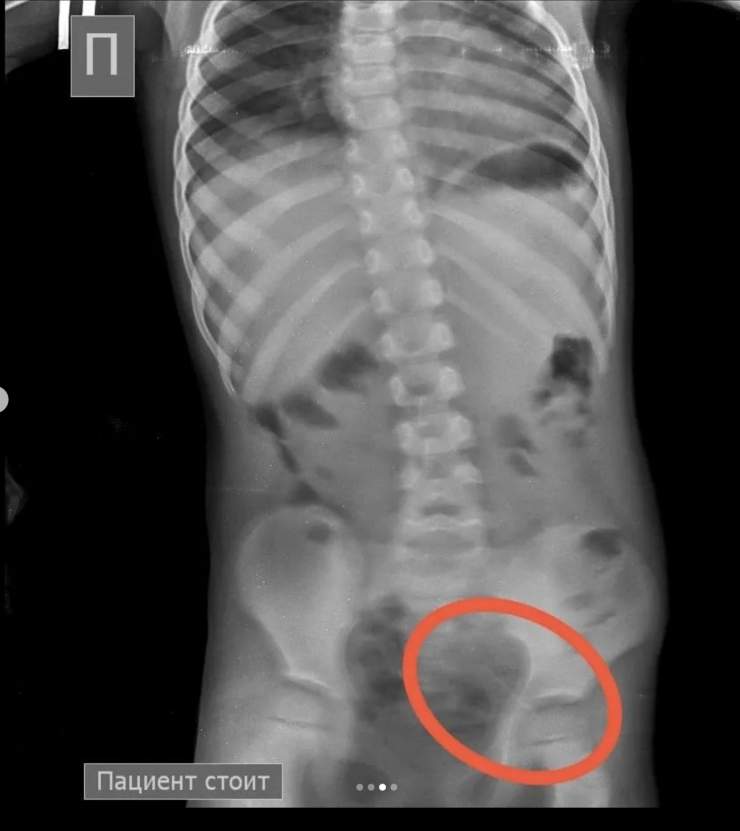

"На обзорной рентгенограмме брюшной полости был обнаружен бегунок и, предположительно, две швейные иглы в проекции желудка. При проведении процедуры ЭФГДС из желудка удалена одна игла, бегунок отсутствовал. Пациент был оставлен в хирургическом отделении Жамбылской областной многопрофильной детской больницы под наблюдением специалистов", - рассказали врачи детской больницы.

В результате бегунок со стулом вышел самостоятельно. В то же время другая игла не выходила.

Фото Instagram/densaulyk.zhambyl